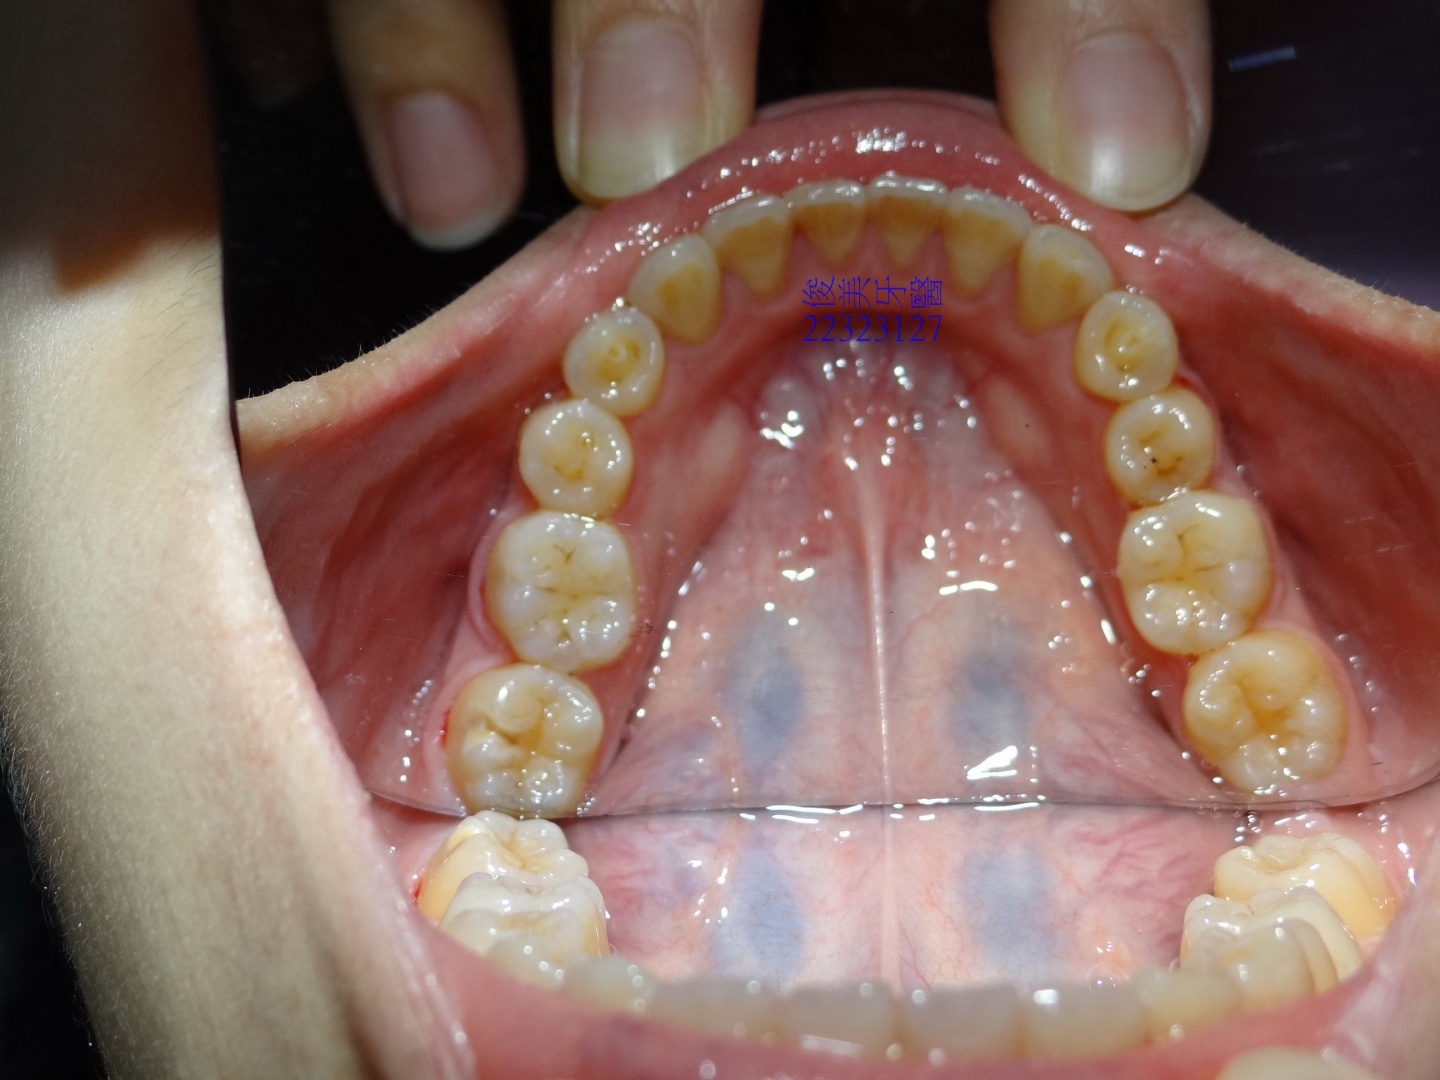

![]() 患者於門診中表示,牙齒很擁擠,想要改善;經醫師門診後,建議患者進行矯正治療即可改善。 ![]() 牙齒重疊... ![]() 有深咬現象... ![]() 上顎狀況... ![]() 下顎狀況... ![]() 左側咬合,牙齒往舌側傾斜...... . ![]() 右側咬合,牙齒往舌側傾斜...... ![]() 治療中....擁擠和深咬已改善.... ![]() 牙齒往後移.....將牙齒齒軸回正一點。 ![]() 治療結束,拆除矯正器了............. ![]() 患者好開心......牙齒整齊後,笑容更可愛了。 ![]() 也沒有暴牙的狀況。 ![]() 上顎牙弓狀況。 ![]() 下顎牙弓狀況。 ![]() 右側咬合狀況。 ![]() 左側咬合狀況。 ![]() 已拆除超過5年,依舊配戴維持器,保持最佳狀態。 |